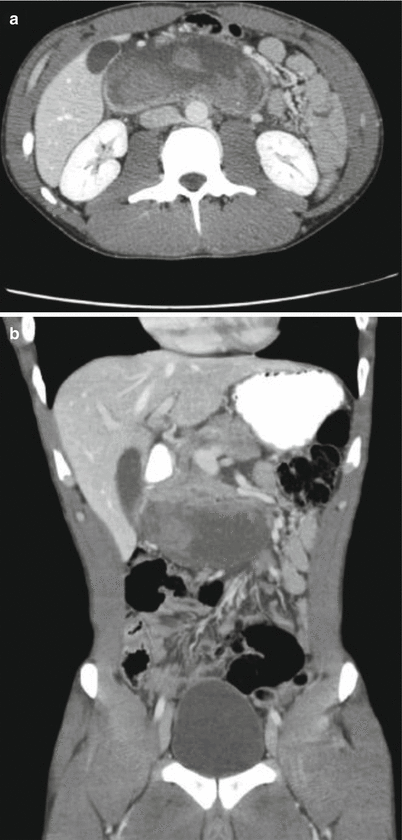

Fig. 46.3

(a, b) Axial and coronal cut of a massive duodenal hematoma. Despite its size the patient had no complaints except mild epigastric pain and gastric outlet obstruction. He was managed nonoperatively with nasogastric tube drainage and the obstruction eventually resolved on post-trauma day 23